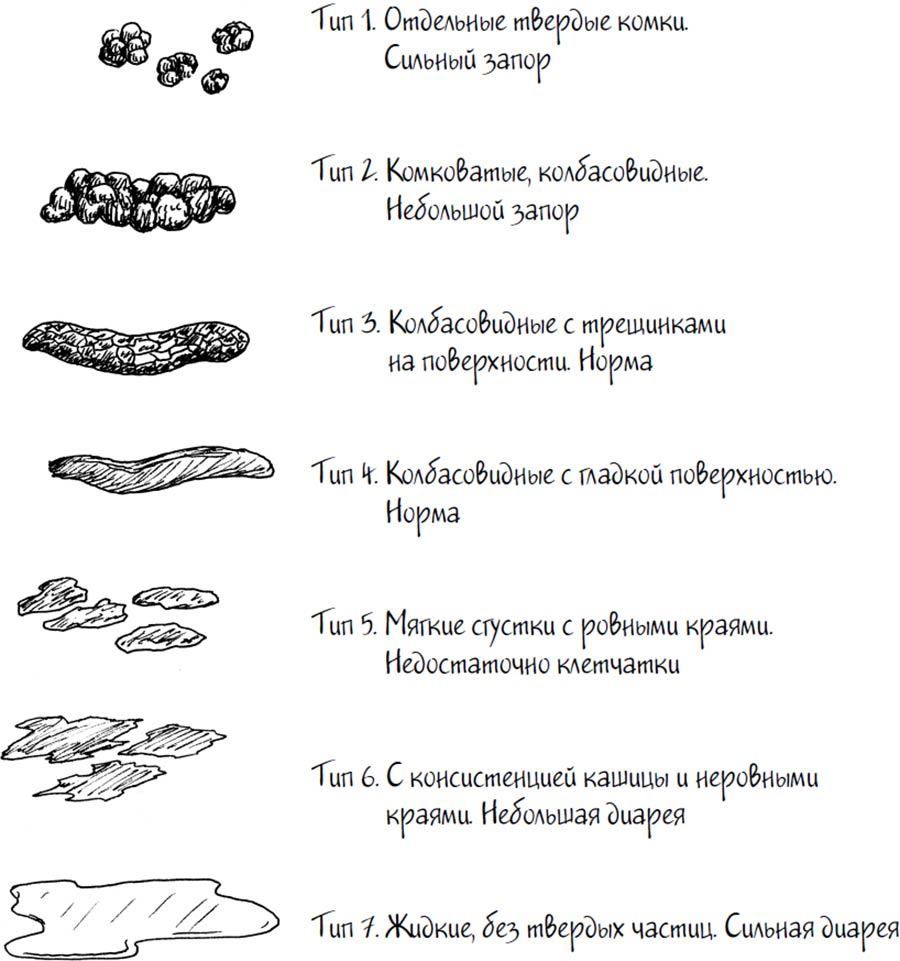

Полезным инструментом для родителей, которые хотят больше знать о фекалиях своих детей, является Бристольская шкала формы кала. Она представляет собой иллюстрации двух английских врачей: они нарисовали несколько колбасок и лужиц, чтобы показать, что следует считать нормальными или ненормальными фекалиями. Эти врачи решили не называть свое «открытие» в честь себя, что, на наш взгляд, можно понять. Возможно, им не нравился город Бристоль, раз уж инструмент для определения качества пищеварения они назвали в честь него. Что на самом деле интересно, так это то, что он также известен под названием «шкала Мейерса», хотя никто с такой фамилией (насколько нам удалось выяснить) никакого отношения к этой шкале никогда не имел. Мы подозреваем, что этот Мейерс, возможно, был врачом-конкурентом или же с ним изменила супруга одного из открывателей шкалы.

Тип фекалий 1 и 2 – прекрасные иллюстрации того, что выходит из нас после запора. Маленькие дети умеют так немного, что едва ли смогу осознать и сообщить, что у них запор, и их кал порой – единственная разгадка. Типы 3 и 4 – примеры нормального стула. Тип 5 встречается достаточно редко, ведь с серьезным недостатком клетчатки легко справиться. Типы 6 и 7 – диарея. Они могут свести анус с ума.